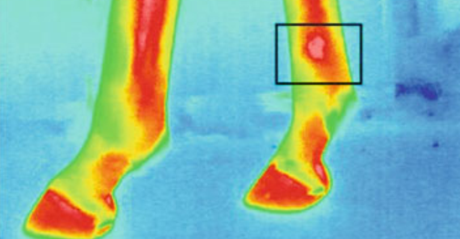

圖為動(dòng)物測溫儀的馬蹄熱成像

屠宰前動(dòng)物的壓力水平對肉質(zhì)至關(guān)重要。壓力水平與動(dòng)物的血液和體溫相關(guān)。因此,重要的是監(jiān)視并應(yīng)對例如溫度升高的溫度。在運(yùn)輸過程中,測量豬耳朵的溫度,發(fā)現(xiàn)溫度與皮質(zhì)醇的濃度和肌酸激酶的活性呈正相關(guān)。例如,診斷馬匹的行走時(shí),動(dòng)物測溫儀熱成像會(huì)很有用。建議使用熱成像來檢測炎癥和其他異常情況,特別是在馬的腿和蹄中。并且也已經(jīng)進(jìn)行了對諸如蛙等外熱動(dòng)物的熱力學(xué)特性的分析。測量了從8℃(人工冬眠)到23℃(人工喚醒)加熱過程中青蛙不同身體部位的溫度。在這樣的實(shí)驗(yàn)中,動(dòng)物測溫儀進(jìn)行測量而不會(huì)傷害或接觸動(dòng)物是一個(gè)很大的優(yōu)勢。